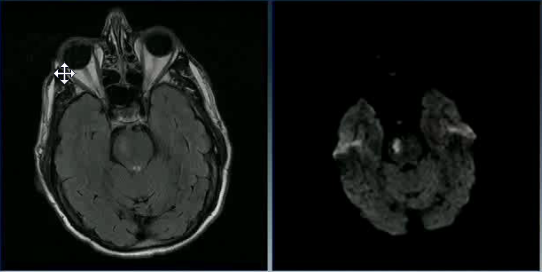

A 20 year old man tries to commit suicide by hanging himself. He is cut down after several minutes and is pulseless. He is resuscitated and regains a heartbeat and respiratory drive and cough to suctioning. Three days later, his exam has not changed. His MRI is attached.

What is the etiology of his brain injury?

Global hypoxia due to asphyxiation and compression of all four major vessels to the brain.

What areas or layers of the cerebrum are affected?

Lamina 3-5 of the entire cerebrum. These lamina are particularly sensitive to hypoxia and die earlier than other areas of the brain.

Why are the ventricles and sulci barely visible in the MRI?

The ventricles and sulci have been compressed by widespread cortical edema

When must this MRI have been taken? Why?

The MRI must have been taken a few days after the injury; cortical edema takes days to show up. Glial cells and astrocytes are able to survive longer (20-30min) during ischemia than neurons (6-10min); their (proportionately greater) survival kept most of the brain’s structure intact despite widespread neuronal death.